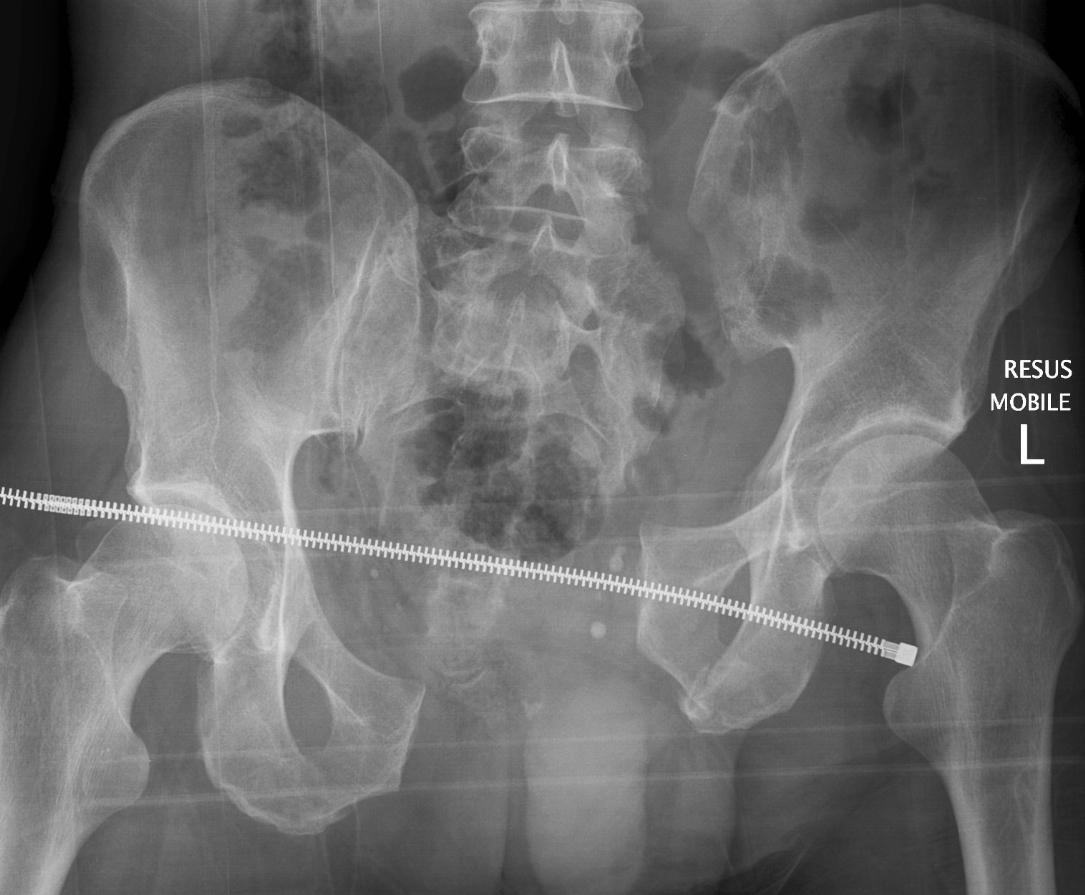

Pelvis Severe Trauma